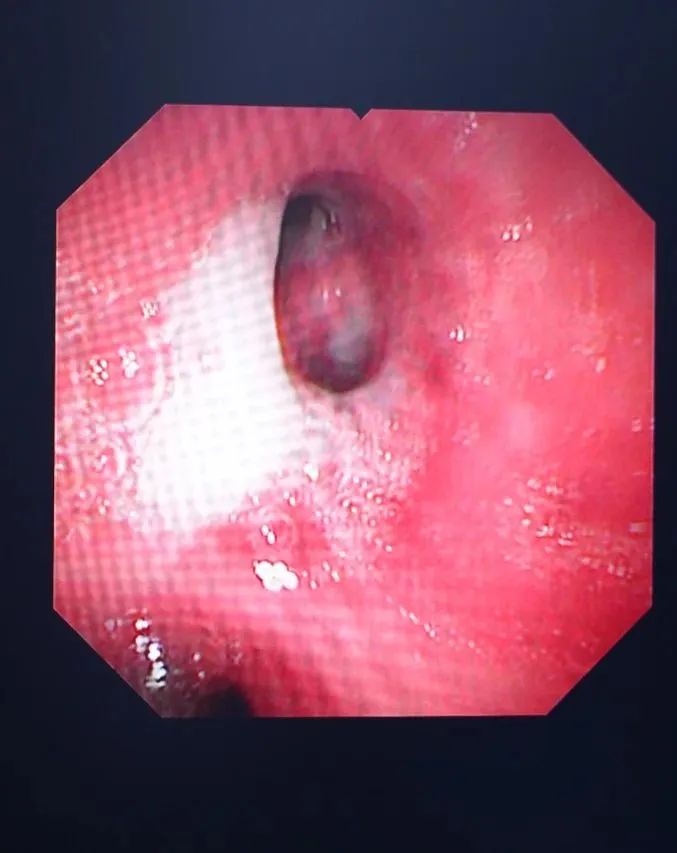

清理氣管分泌物

?支氣管鏡檢查就是將細(xì)長的支氣管鏡經(jīng)口或鼻置入患者的下呼吸道,醫(yī)生可以直觀地觀察到氣管和支氣管病變,并根據(jù)病變做出判斷。是呼吸系統(tǒng)疾病臨床診斷和治療的重要手段,臨床應(yīng)用廣泛。